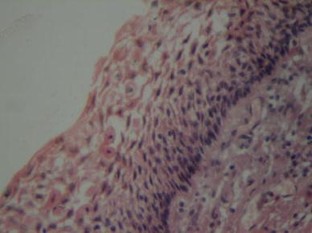

A Study on Dentigerous Cystic Changes with Radiographically Normal Impacted Mandibular Third Molars

Dentigerous cyst develops in the follicular tissue surrounding the impacted lower third molar. A study was carried out to know the incidence of Association of Dentigerous cyst with radiographically normal impacted lower third molars and to draw the attention of the Oral Surgeons towards the prophylactic removal of impacted third molars.

A prospective study was done on 30 patients with impacted lower third molars which were indicated for extraction. The follicle tissue surrounding the impacted tooth was subjected for histopathologic investigations. Only those teeth with a radiographic finding of pericoronal space of less than 2.5 mm were considered. Two Oral Pathologists reviewed the slides for any changes suggestive of cystic pathology.

Pathologic changes suggestive of Dentigerous cyst was found in 7 of the 30 follicular tissue sent for histopathologic testing. It was found to be statistically significant (P < 0.001).

This study shows statistically high incidence of Dentigerous cyst association with radiographically normal impacted lower third molar teeth. Hence the Oral and Maxillofacial surgeons should consider histopathologic evaluation and radiographic diagnosis in the management of impacted lower third molars. Prophylactic extractions of normal impacted lower third molars should be considered as a treatment option.